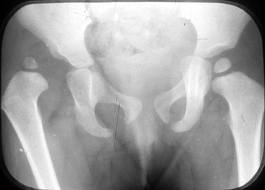

With hip dysplasia, the surfaces of the hip joint (the femoral head, or “ball” and the acetabulum or “socket”) may experience incomplete contact (subluxation) or a total loss of joint contact (dislocation). The severity of hip dysplasia is rated according to the extent of contact between the femoral head and the acetabulum and signs of osteoarthritis as viewed on x-ray. Although hip dysplasia is typically first recognized in infants, mild hip dysplasia may not be diagnosed until adulthood. Hip dysplasia is a common cause of hip pain in young adults and, if left untreated, can lead to early degenerative changes (osteoarthritis) of the hip joint. Hip dysplasia is a cause of degenerative changes in the hip leading to hip replacement surgery in adults (Millis).

Tests: Abnormalities of the hip joint may be viewed on x-rays taken in a neutral standing (weight bearing) position; in a “false profile” view, in which the individual stands at an angle to the imaging plate; and also in a position of abduction and internal rotation (AIR) to assess alignment of the femoral head within the acetabulum (Sucato). Ultrasound scanning is commonly used in assessment of the infant hip, but is less commonly used for adult diagnosis. Rarely, computed tomography (CT) scan and magnetic resonance imaging (MRI) may be done to rule out potential tears of the cartilaginous ring that surrounds the acetabulum (acetabular labrum), other cartilage defects, and other soft tissue disorders that may exist concurrently with hip dysplasia.